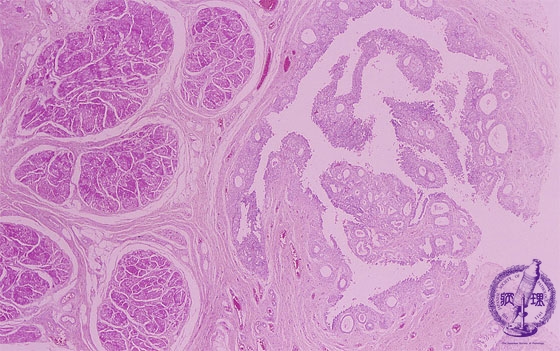

Microscopic findings (HE, high power view): Cystitis cystica. The von Brunn’s nests are dilated to form cystic lesions (yellow arrows).

Click the image to see the enlarged image.